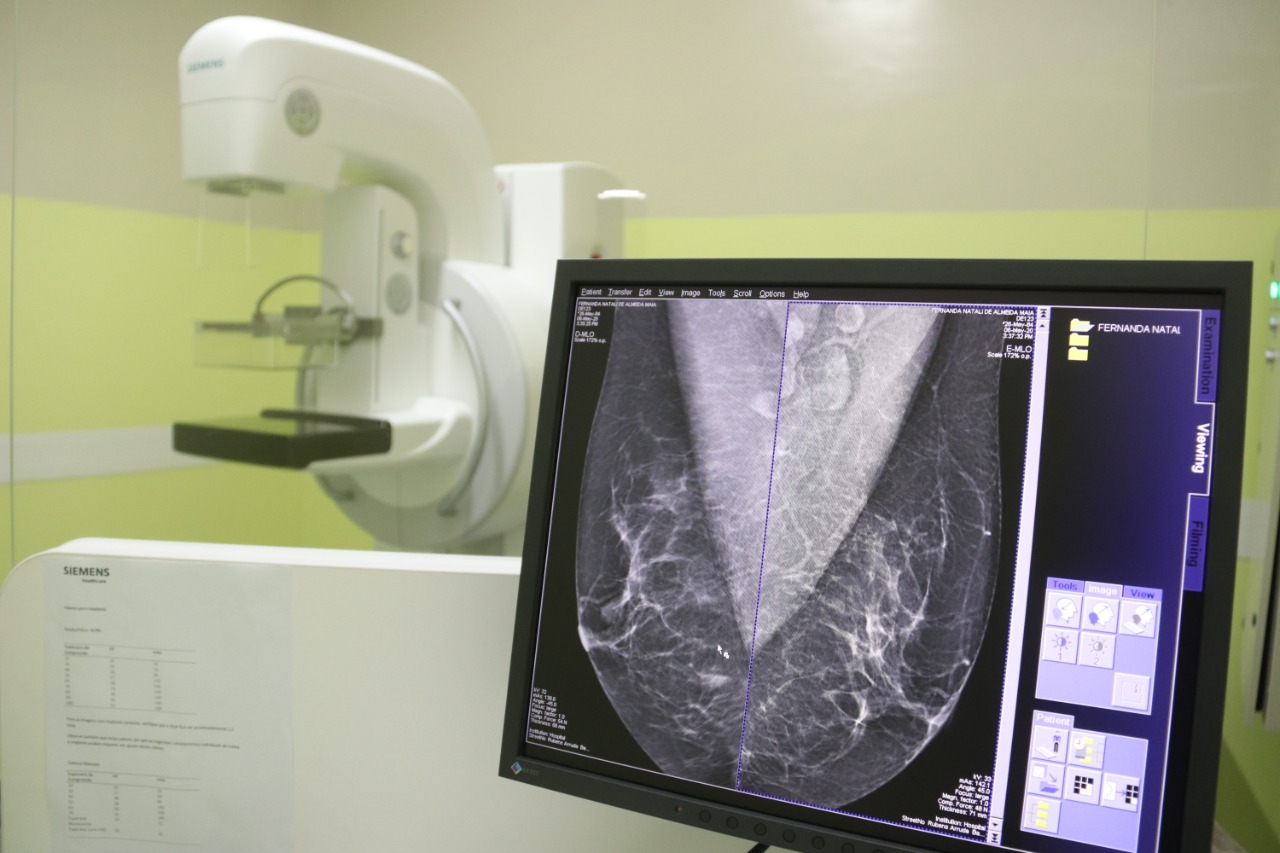

Na busca de ampliação no número de exames e o rastreamento precoce do câncer de mama nas mulheres, a Prefeitura também contará com um mamógrafo digital, adquirido pela Pacaembu Construtora por meio de recursos advindos de contrapartida com o Estudo de Impacto de Vizinhança – EIV. A empresa também foi responsável pelo pagamento da reforma e adequações das salas onde foram instalados os aparelhos, além da aquisição de equipamentos de informática e licenças de software.

As imagens nos exames de mamografia e tomografia são de alta definição e com baixa incidência de radiação, proporcionando maior segurança para o paciente e a equipe técnica.

Por meio da tecnologia no sistema de informatização, existente em toda a rede pública municipal, os profissionais podem acessar as imagens imediatamente após sua execução, via internet, em qualquer serviço de saúde. Oferecendo facilidade e agilidade no diagnóstico e tratamento dos pacientes, redução de custo, além de ser uma ferramenta de planejamento para a gestão pública